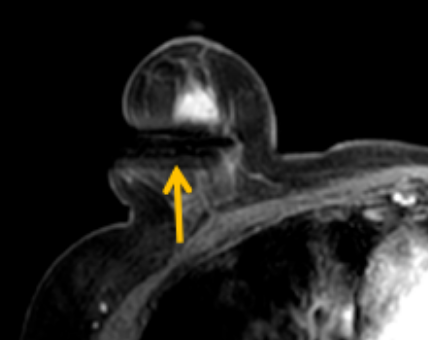

陳寶瑩評估圖像后發(fā)現(xiàn)病變?yōu)閮H僅在磁共振增強(qiáng)時顯示,為非腫塊樣病變,比較散,必須取得足夠多的組織才能確保病理檢查的準(zhǔn)確性,常用的核芯針活檢獲取的組織較少,因此最終確定了磁共振引導(dǎo)下行真空輔助抽吸旋切活檢。取得患者及家屬認(rèn)可后,陳寶瑩帶領(lǐng)團(tuán)隊開始進(jìn)行術(shù)前準(zhǔn)備。

針對患者乳房小固定難度大這一問題,陳寶瑩通過巧妙體位和固定器的調(diào)整,順利固定好乳房。經(jīng)過磁共振多模態(tài)掃描,陳寶瑩找出病變活性成分相對集中區(qū)域,精準(zhǔn)確定穿刺路徑,置入引導(dǎo)針、旋切針,到位后多角度旋切取出足量組織,拔除旋切針后即時行磁共振掃描,精準(zhǔn)取得組織且術(shù)區(qū)出血很少,遂加壓包扎,整個過程非常順利,旋切活檢后患者回家休息。兩天后隨訪,李女士沒有任何不適,五天后皮膚上幾毫米的小切口已經(jīng)愈合。最終病理結(jié)果證實為乳腺導(dǎo)管原位癌,為早期乳腺癌,為患者后續(xù)針對性治療奠定了基礎(chǔ)。